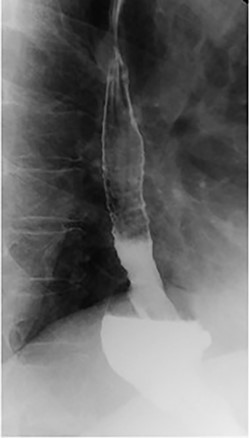

Preoperative endoscopy (post gastroplasty) showing the body of the stomach without restrictive sleeve appearance.

Patient subsequently underwent a robotically assisted laparoscopic paraesophageal hernia repair with mesh, partial gastrectomy with removal of gastric foreign bodies, and flexible endoscopy. Intraoperatively via initial laparoscopic approach, there was only noted to be small dimples along the greater gastric curve without any noticeable plication (Fig. 3). The stomach was twisted up into the hiatal hernia. Multiple permanent sutures with T-fasteners were seen on endoscopy, and attempts were made to remove these endoscopically without success. These sutures were not of full thickness, so a gastrotomy was made to remove them. Partial gastrectomy was performed, including the fundus. The diaphragm was repaired with interrupted silk sutures and reinforced with a bioabsorbable mesh. The patient recovered well and was discharged home on postoperative day two tolerating a diet. She was seen at follow-up with complete resolution of her preoperative symptoms.